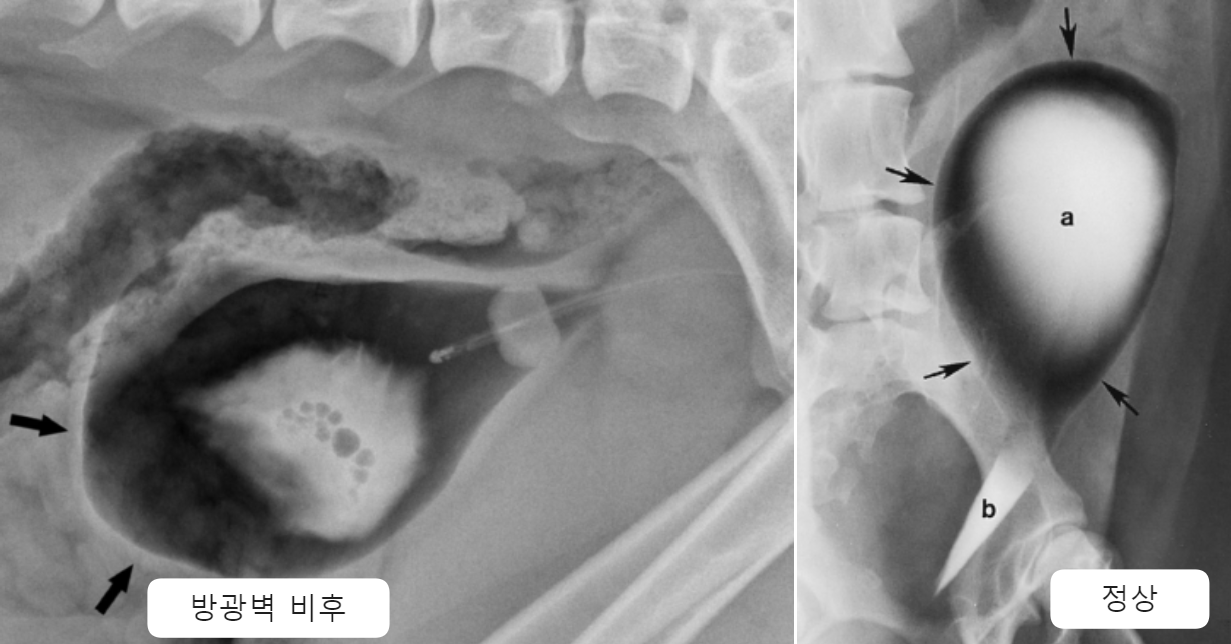

| Radiographs _Cystitis | |

![]() | - ์์ ํฌ๊ธฐ์ ๋ฐฉ๊ด - ๋ฐฉ๊ด๋ฒฝ์ ๋นํ(thickening), irregularity |